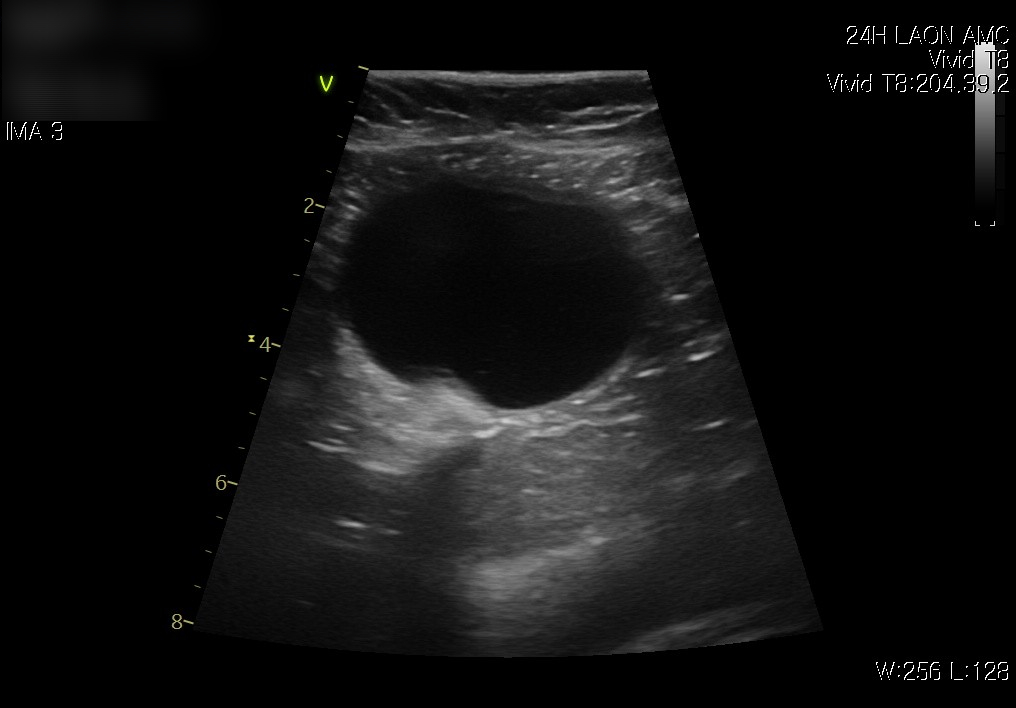

치료 후 방광 요도(좌) / 치료 후 방광 초음파 사진 / 출처: 라온동물메디컬센터

추적 초음파 검사에서도 방광 내 염증으로 인한 찌꺼기도 사라졌으며,  소변이 정상적으로 배출되는 모습이 확인되었습니다.  보호자님께는 방광염 재발을 예방하기 위해 방광염 처방사료의 식이 교체와 함께, 방광 보조제 급여를 권장드렸습니다.